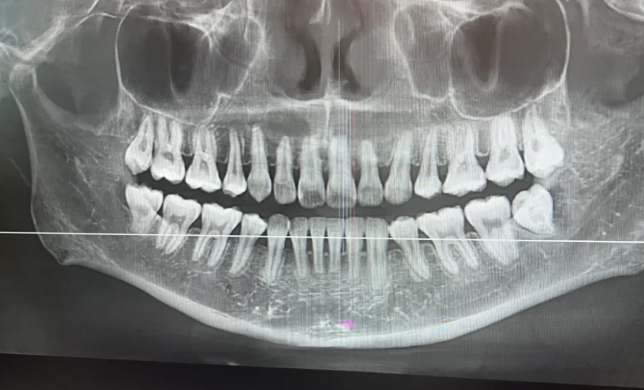

穗華口腔部分項(xiàng)目確實(shí)支持免費(fèi)拍片,但并非所有拍片項(xiàng)目都免費(fèi),具體需結(jié)合就診項(xiàng)目、活動(dòng)規(guī)則及分店政策判斷。從親測(cè)體驗(yàn)與用戶反饋來(lái)看,穗華口腔的免費(fèi)拍片主要集中在初診評(píng)估、特定治療前置檢查及新用戶活動(dòng)中,且以全景片、側(cè)位片、小牙片等基礎(chǔ)拍片類型為主,高端的CBCT(錐形束CT)通常需額外收費(fèi)。

比如頭一次到穗華口腔詢問(wèn)正畸或種植牙項(xiàng)目時(shí),醫(yī)生為了評(píng)估牙槽骨條件、牙齒排列情況,會(huì)開具全景片(顯示全口牙齒與牙槽骨)和側(cè)位片(顯示頜面骨骼輪廓)的檢查單,這兩項(xiàng)通??擅赓M(fèi)享受。親測(cè)流程如下:到店后先登記個(gè)人信息,與醫(yī)生面診說(shuō)明需求,醫(yī)生根據(jù)情況開單,然后到放射科拍片,大約10分鐘即可出報(bào)告,全程無(wú)需支付拍片費(fèi)用。

初診正畸/種植評(píng)估:頭一次詢問(wèn)牙齒矯正(金屬托槽、隱形正畸等)或種植牙的患者,醫(yī)生需要通過(guò)拍片了解牙齒擁擠度、牙槽骨厚度、頜面關(guān)節(jié)情況,此時(shí)全景片 + 側(cè)位片一般免費(fèi);若需進(jìn)一步檢查牙槽骨密度(如種植牙患者),CBCT可能需收費(fèi),費(fèi)用約300 - 400元。